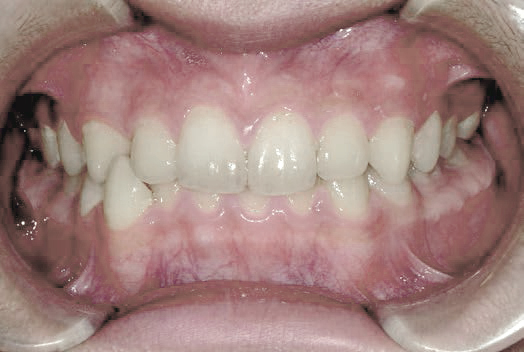

上あごの成長が少なく、特に前歯のガタガタが目立っていました。口呼吸のクセや飲み込み方に良くないクセが確認されました。

治療を終えて

マイオブレイスとBB1装置で上あごの成長を助け、鼻呼吸や正しい飲み込み方を身につけることで、きれいな歯並びとしっかり噛めるお口に変わっていきました。

姿勢やお口の機能を正しく整えたので、後戻りしない綺麗な歯並びを維持できています。もちろん非抜歯です。

主訴・治療内容 当院と交流のある歯科医師の先生が、ご自身のお子さまの治療を任せてくださいました。

「難しい歯並びでも永久歯を抜かず、全身の健康と顔立ちも考えて治療してくれる」と信頼していただいて治療開始。